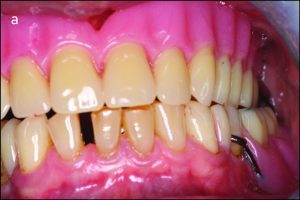

In bilateral balanced occlusion, during lateral movement, there are simultaneous bilateral contacts of opposing posterior teeth on both the working and balancing sides. For example, during a left lateral movement, antagonist tooth contacts occur on the working side primarily through the buccal cusps in the posterior region (Figure 9-4a), while on the opposite side, the buccal cusps of the mandibular teeth are in contact with the palatal cusps of the maxillary teeth. This prevents the right side of the removable prosthesis from lifting off the tissue (Figure 9-4b).

Figure 9-4. In bilateral balanced occlusion during left lateral movement: b) On the non-working side, antagonist contacts occur between the palatal cusps of the maxillary teeth and the buccal cusps of the mandibular teeth.